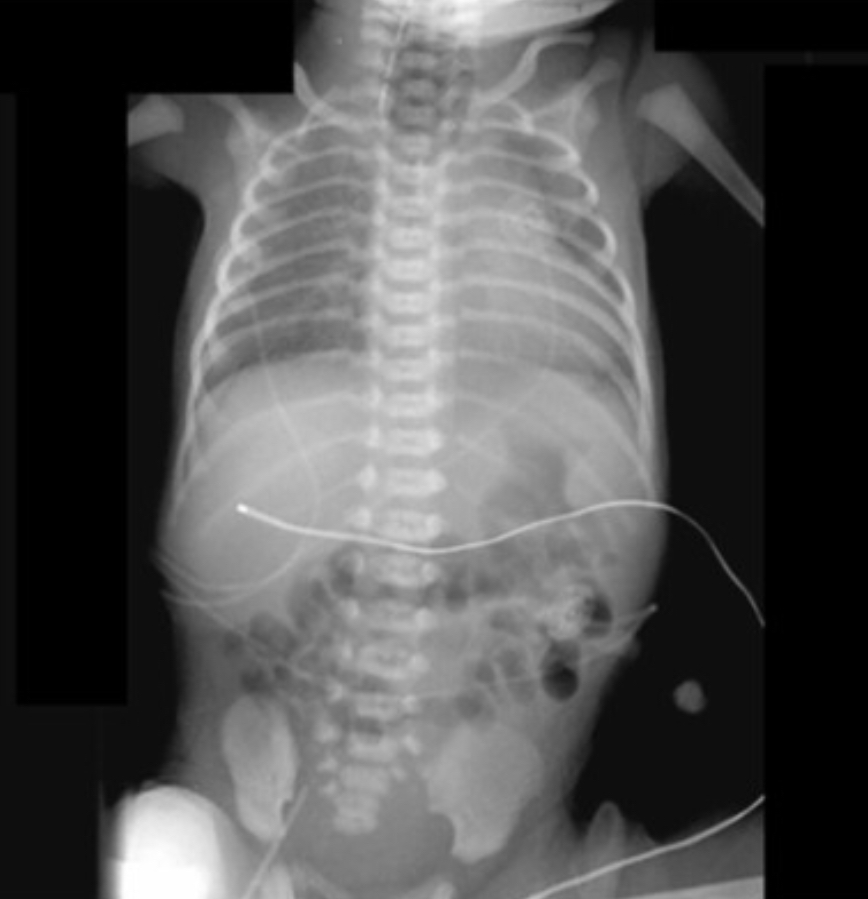

Dumbbell shaped mass extending from intra-abdominal into large exophytic perineal mass in a newborn.

may have cystic elements

sacrococcygeal teratoma

–> high rate of in utero hydrops and hemorrhage –> can be controlled at birth with immediate resection of exophytic component

rhabdomyosarcoma can also present as large pelvic mass but would be older child (2-6 years) and wouldn’t extend into perineum

infantile fibrosarcoma can have solid and cystic components in a newborn but more often in head/neck and extremities